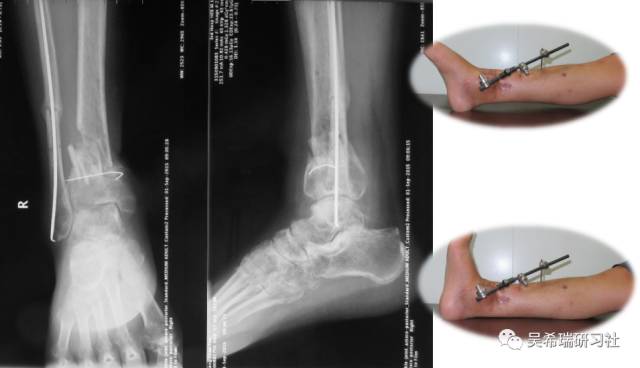

病例8

双下肢车祸外伤保肢的理由是足底皮肤好

TIPS:清创&盐水冲洗(不用双氧水)VSD骨水泥技术&开放植骨单边外固定架(下胫腓联合固定)早期下地 生理应力 + 机械应力游离植皮 / 不用皮瓣清创时游离皮质骨去除胫跖骨牵引技术防治&纠正足下垂